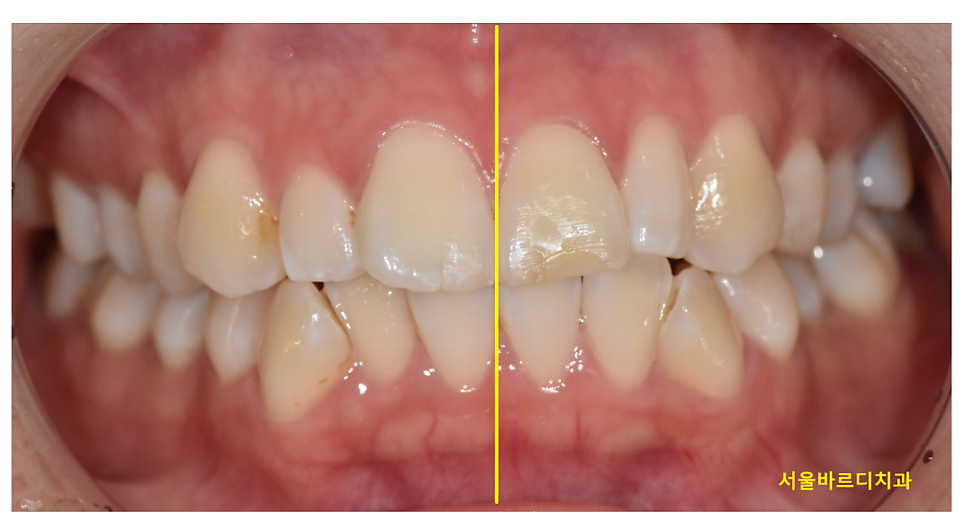

치아의 중심선이란,

위 앞니 두 개의 중앙과 아래 앞니 두 개의 중앙이 일직선상에 있는지를 의미합니다.

250215 중심선은 맞지만 부정교합입니다.

이상적인 교합에서는 이 중심선이

코 가운데와 일치하는 것이 가장 이상적이지만,

현실에서는 그렇지 않은 경우가 훨씬 많습니다.

250328 정중선이 안맞는 경우

사람 얼굴이 비대칭일 수도 있고

치아가 결손됐을 수도 있고

여러 원인으로 중심선이 1-2mm 정도 어긋나서

치료가 마무리 될 수 있는데요.

중심선이 어긋나있다고 반드시 교정이 잘못됐다고 단정할 수는 없습니다.